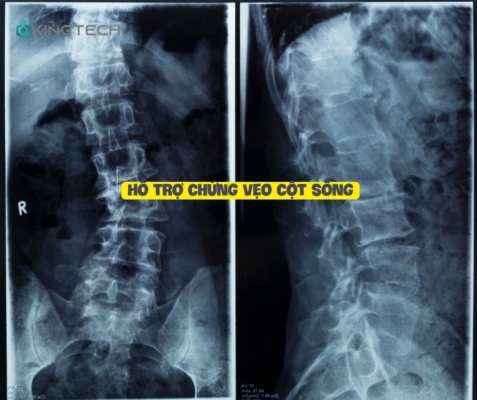

5. Hỗ trợ chứng vẹo cột sống

Tư thế cây cầu, một bài tập yoga cổ điển, không chỉ là một phương pháp tập luyện, mà còn là một liệu pháp chữa lành cho những ai đang chịu đựng những cơn đau từ vẹo cột sống. Vẹo cột sống không chỉ là một vấn đề về hình dạng, mà còn ảnh hưởng đến sự cân bằng và chức năng của cơ thể, khiến các đốt sống và cơ xung quanh không thể hoạt động hài hòa.

Khi thực hiện tư thế cây cầu, bạn không chỉ đang tạo ra một sức mạnh mới từ bên trong, mà còn đang dần dần định hình lại cấu trúc của cột sống. Động tác này giúp giãn và củng cố các cơ liên quan, từ đó giảm bớt áp lực lên cột sống, mang lại sự linh hoạt và giảm đau hiệu quả.